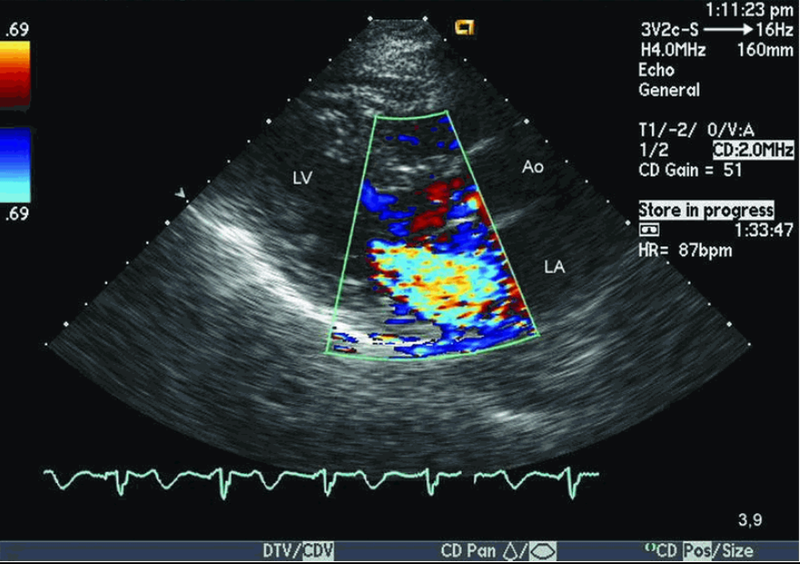

Siêu âm Doppler đóng vai trò quan trọng trong sàng lọc tiền sản giật, đánh giá tuần hoàn tử cung - nhau thai và đánh giá sức khỏe thai nhi, bao gồm cả tuần hoàn thai nhi. Phương pháp không xâm lấn này hỗ trợ bác sĩ chuyên khoa có thể xác định các rủi ro tiềm ẩn cũng như đảm bảo sức khỏe cho cả mẹ và bé.

Khi nghi ngờ có khuyết tật tim bẩm sinh, siêu âm tim thai chi tiết sẽ có tác dụng. Phương pháp chuyên biệt này sẽ đi sâu vào tim thai nhi, kiểm tra hình thái, cấu trúc và hoạt động của nó để phát hiện những bất thường bẩm sinh (nếu có), dựa trên đó có thể đưa ra những biện pháp can thiệp phù hợp, đảm bảo sức khỏe tim mạch của bé.